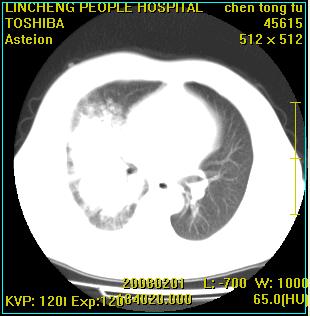

患者,男性,62岁。主因头晕,发热,咳嗽6天,高热达39度,esr19mm/h,wbc 3.9×10 9/l

大叶性肺炎并胸膜炎

右肺大叶性肺炎,胸腔积液。建议痰检。

实变区见空气支气管征,支气管通畅,考虑为大叶性肺炎,右侧少量胸水

1)考虑为:右肺感染性病变。建议:抗炎治疗复查。2)右侧少量胸腔积液。

考虑为右肺大叶性肺炎,胸腔积液,建议必要时纤维支气管镜检查,以排除肿瘤性病变。

右肺炎症并右侧胸腔少量积液。

大叶性肺炎并胸膜炎、胸水。

考虑为右肺大叶性肺炎伴少量胸腔积液,建议复查,如病变不吸收或吸收不明显,建议纤维支气管镜检查,除外细支气管肺泡癌的可能。

右侧大叶性肺炎,右侧少量胸腔积液.

实变区见空气支气管征,支气管通畅,考虑为大叶性肺炎,右侧少量胸水。